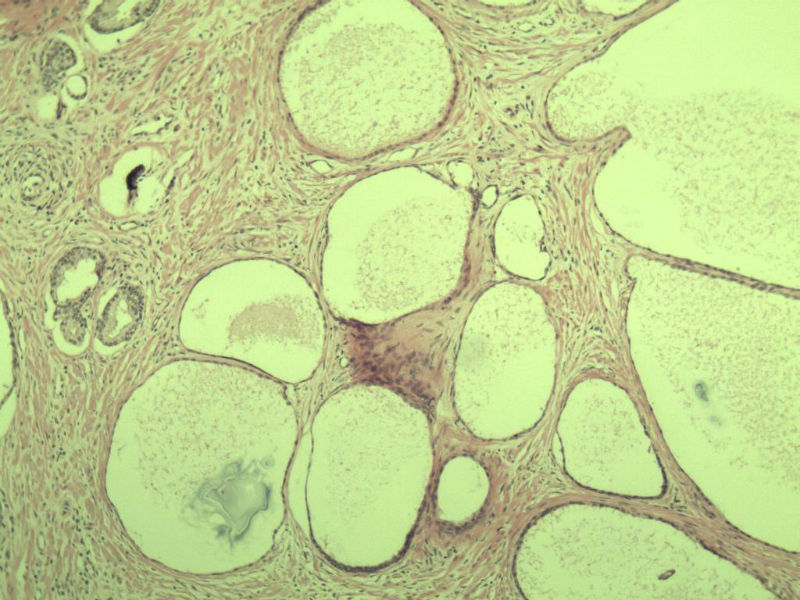

男 75岁 因排尿困难半年行前列腺切除术,体积 4 × 3 × 2.5 cm3,切面灰白,实性,质韧。请各位老师看看 有问题没? 谢谢了!

前列腺增生症伴鳞化

良性前列腺增生

良性前列腺增生伴尿路上皮化生

前列腺增生,有腺瘤样结节形成。

前列腺增生伴尿路上皮鳞化及Brown巢形成,未见恶性。

前列腺结节性增生